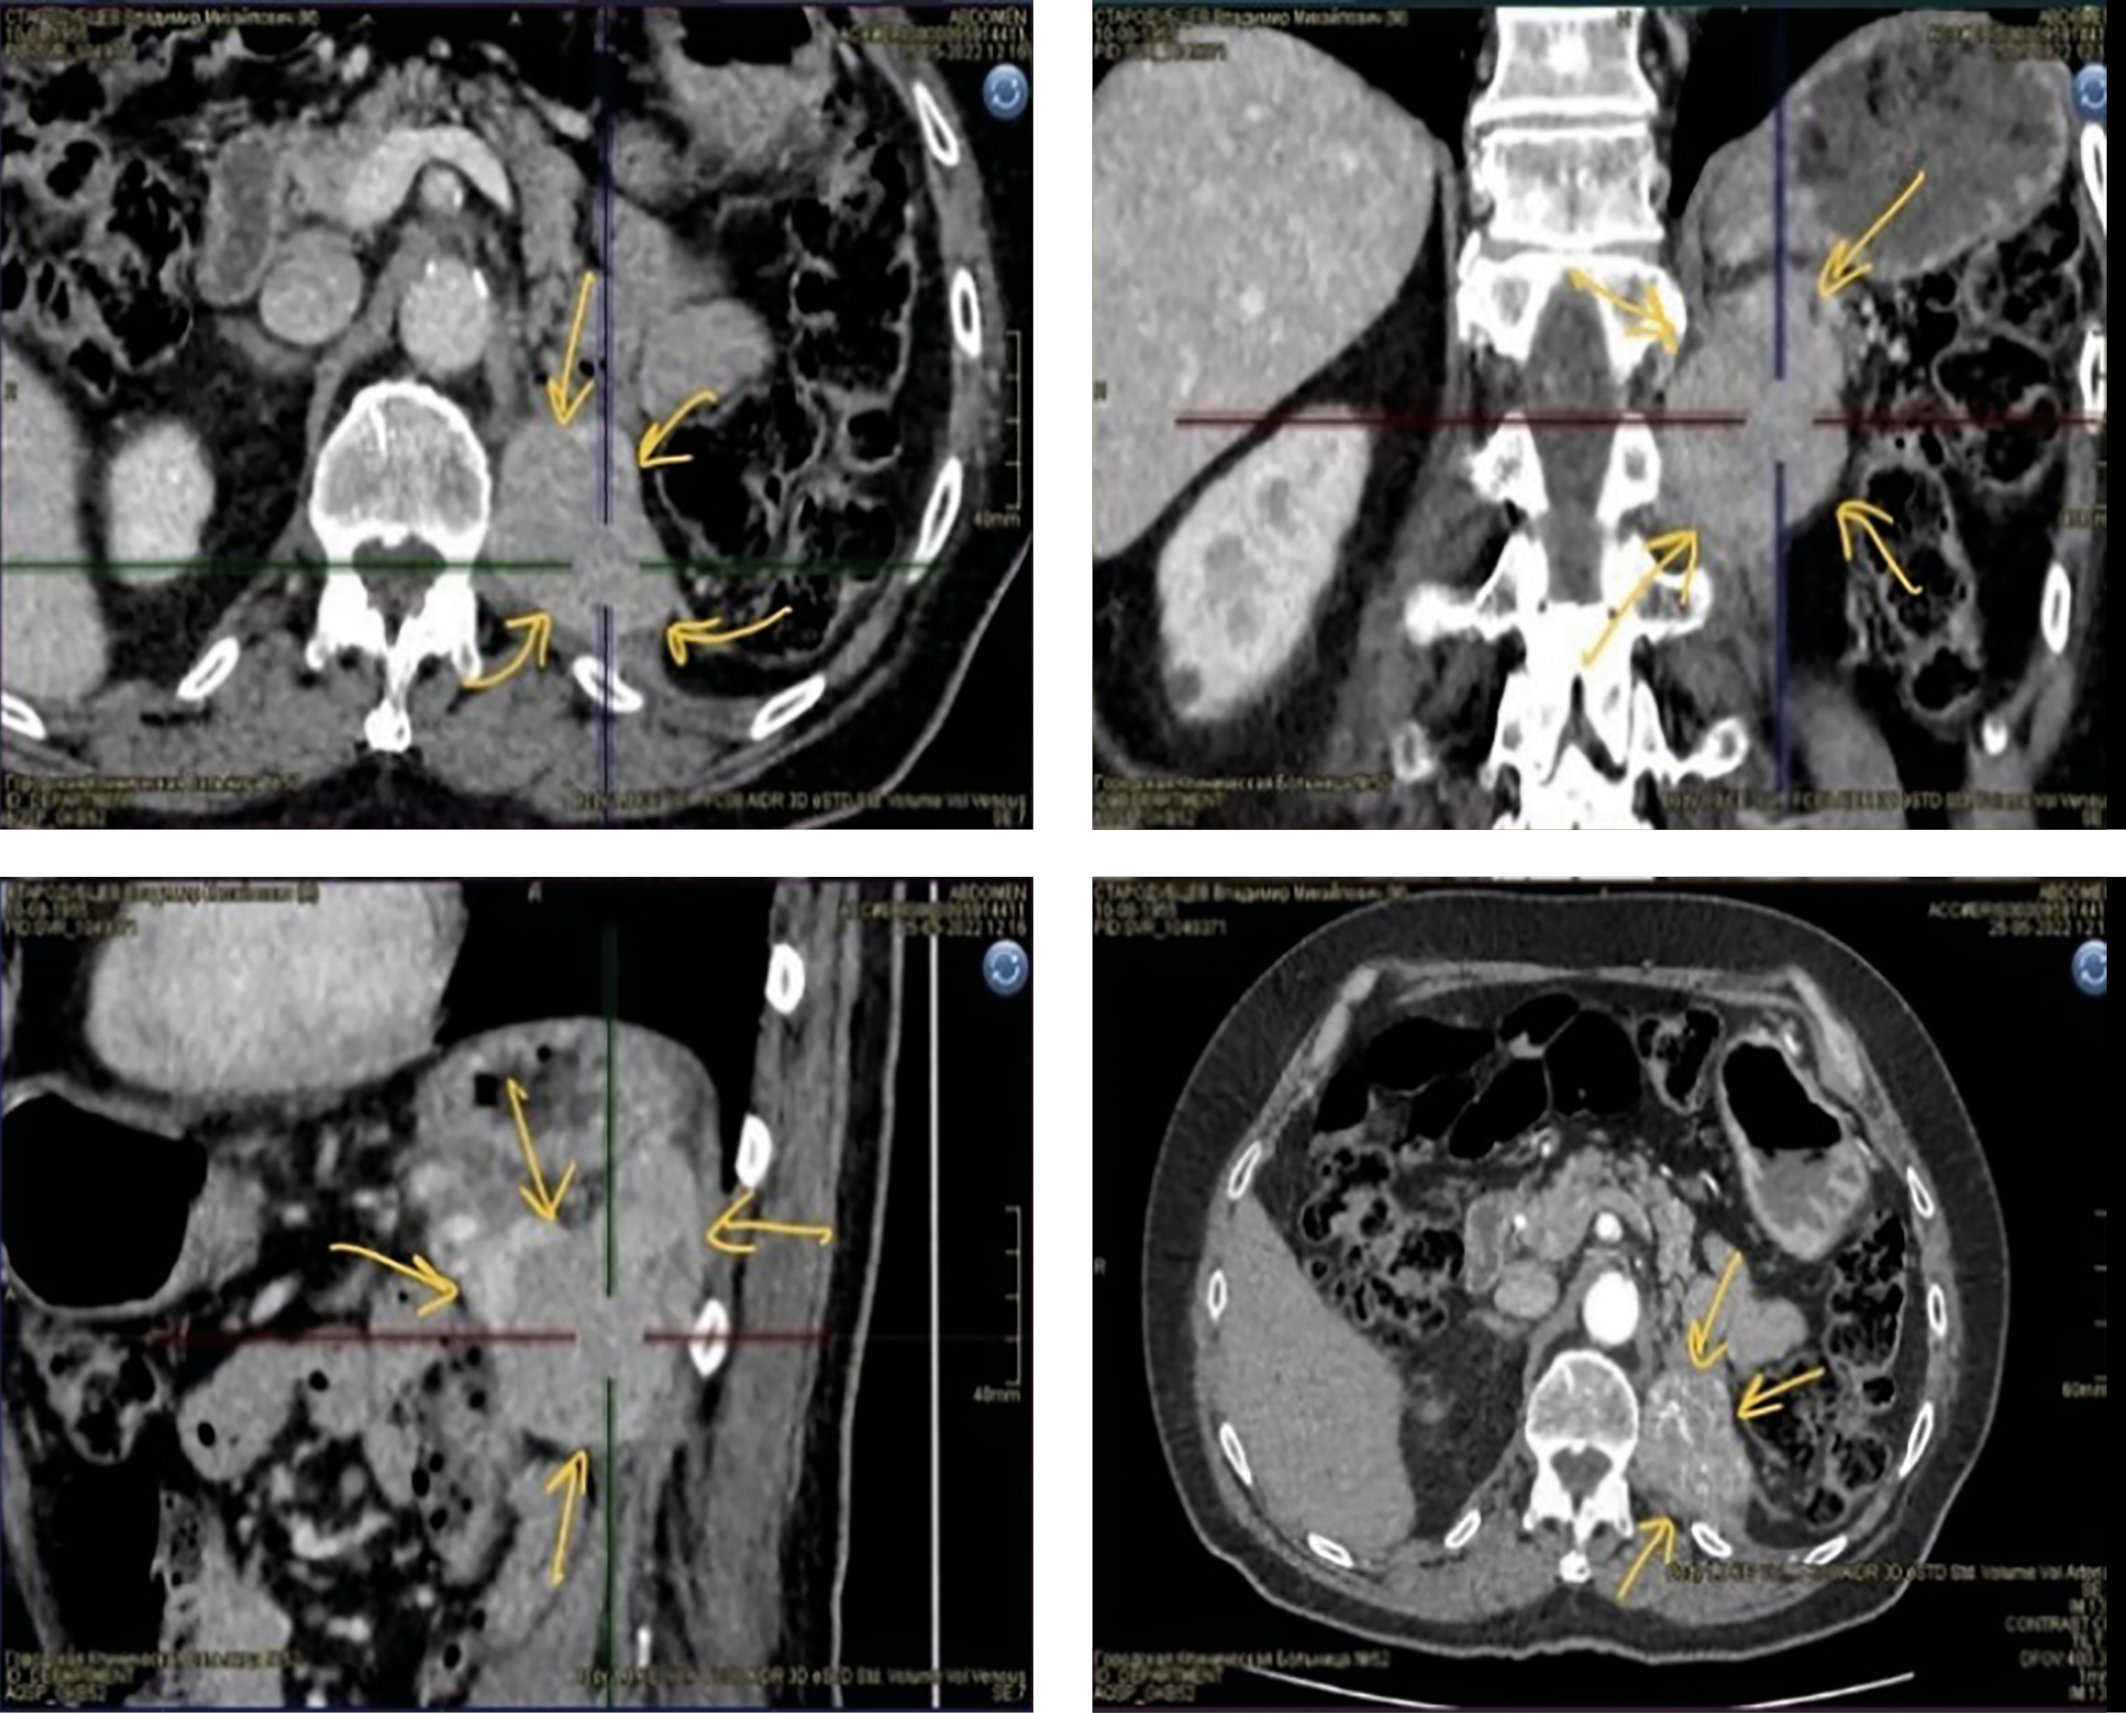

5. Рисунок 5. МСКТ органов брюшной полости в июле 2024 г: множественные имплантационные МТС ПГ по контуру диафрагмы, поясничных мышц, аорты и задней стенки брюшной полости. | |